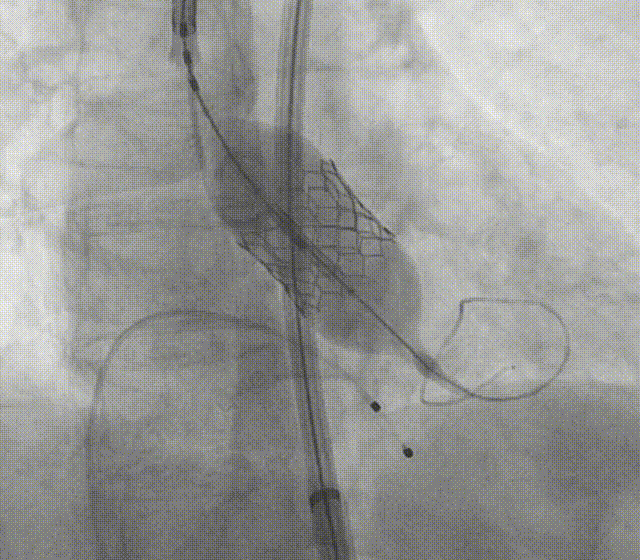

通过支撑导丝,送入23mm SAPIEN 3瓣膜,使用独特调弯功能,保证安全过弓并成功跨瓣;调整至共平面角度,瓣膜到位,快速起搏下-2cc精准释放瓣膜。

图片